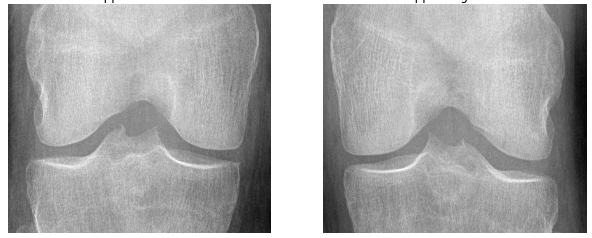

Knee OA develops gradually over years and progresses in stages. In general, the severity of knee OA is divided into five stages. The first stage (stage 0) corresponds to normal healthy knee and the final stage (stage 4) corresponds to the most severe condition (see Figure 2). The most commonly used systems for grading knee OA are the International Knee Documentation Committee (IKDC) system, the Ahlback system, and the Kellgren & Lawrence (KL) grading system. The other widely used non-radiographic knee OA assessment system is WOMAC666Western Ontario and McMaster Universities Osteoarthritis Index, which measures pain, stiffness, and functional limitation. The public datasets, the OAI and the MOST used in this work, are provided with the KL grades and they are used as the ground truth to classify the knee OA X-ray images.

Refer to caption

Figure 2: The Kellgren and Lawrence grading system to assess the severity of knee OA.

The KL grading scale was approved by the World Health Organisation as the reference standard for cross-sectional and longitudinal epidemiologic studies [7, 22, 24, 25]. The KL grading system is still considered the gold standard for initial assessment of knee osteoarthritis severity in radiographs [1, 5, 6, 7]. Figure 2 shows the KL grading system. The KL grading system categorizes knee OA severity into five grades (grade 0 to 4). The KL grading scheme for quantifying knee OA severity from X-ray images is defined as follows [1, 5]:

• Grade 0 : absence of radiographic features (cartilage loss or osteophytes) of OA.

• Grade 1 : doubtful joint space narrowing (JSN), osteophytes sprouting, bone marrow oedema (BME), and sub-chondral cyst.

• Grade 2 : visible osteophytes formation and reduction in joint space width on the antero-posterior weight-bearing radiograph with BME and sub-chondral cyst.

• Grade 3 : multiple osteophytes, definite JSN, sclerosis, possible bone deformity.

• Grade 4 : large osteophytes, marked JSN, severe sclerosis, and definite bone deformity.